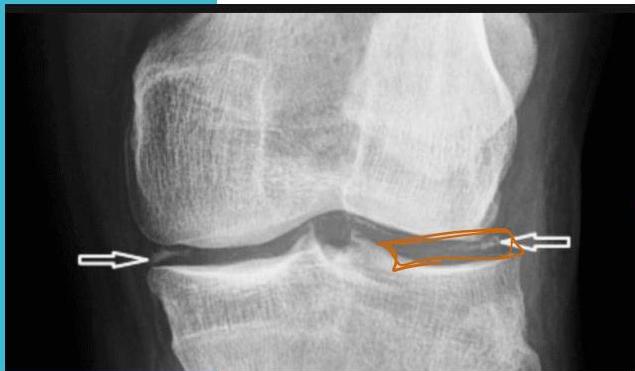

Pseudogout

Healthy Joint

Joint with Pseudogout

chondrocalcinosis